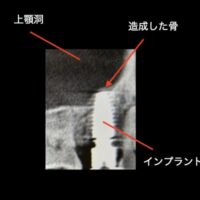

インプラントについてご質問を受けることがあります。その中で当院がもっとも大事だなと思うものをピックアップしました。インプラントを手術するにあたり、歯医者が一番頑張らないといけないのが、インプラントのポジションです。インプラントの位置です。これだけは一度インプラントをお口に入れてしまったら、変更することができません。一回の勝負になります。ですから慎重に、考えに考えて埋入する必要があります。考えて埋入しても手がぶれてしまっては元も子もないです。

- 高精度なシミュレーション:CTデータと口腔内スキャンデータを統合し、インプラントの最適な埋入位置や角度を事前にシミュレーションできます。

インプラント手術にSMOPを入れました。

インプラントがセットした後の写真が以下の通りです。

スクリューリテインで素晴らしい結果となりました。